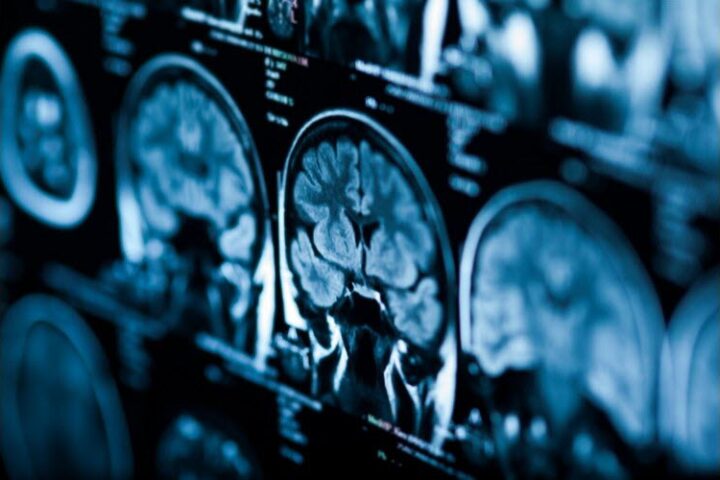

Eric Dane meurt à 53 ans de la maladie de Charcot, la sclérose latérale amyotrophique

L’acteur Eric Dane est mort à 53 ans de la maladie de Charcot. Sa famille a annoncé son décès dans un communiqué jeudi 19 février. Il avait notamment incarné Mark Sloan dans